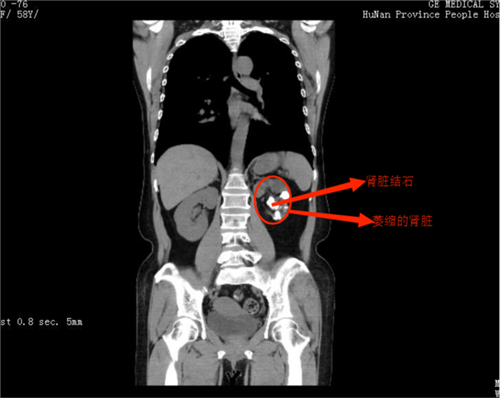

检查结果显示唐女士左肾满是结石,并且已经萎缩

唐女士今年58岁,十多年前偶然发现左肾长有结石,当时结石较小,也没有什么不舒服,“因为不痛就没有管它。”唐女士表示。没想到,今年2月,唐女士在一次体检中的发现其左肾的结石已经疯狂长满整个肾脏,并已经导致左肾萎缩,这才来到湖南省人民医院泌尿外科四病区就诊。

入院后,杨科主任发现,唐女士为左肾多发铸型结石,结石长满整个肾脏,大的结石约3×4cm,左肾萎缩,肾显像结果显示其左肾肾功能几乎完全丧失。考虑结石如果不及时处理,会反复感染,长期刺激可能导致癌变,由于结石无法通过一次手术清除干净,且肾脏几乎没有功能,保肾取石没有意义。经过与唐女士及家人充分沟通,杨科主任团队为唐女士实施了左肾切除手术,手术顺利,经过恢复,唐女士于3月1日出院。